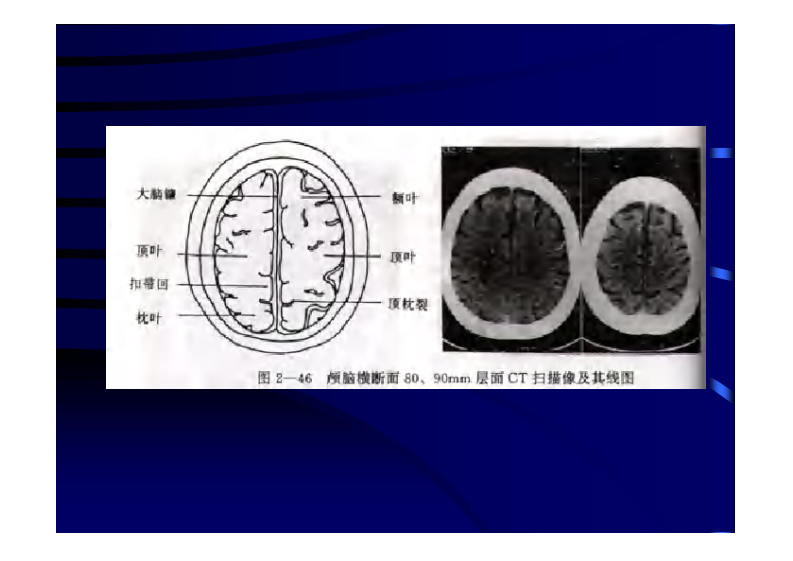

颅脑CT、MRI.pdf